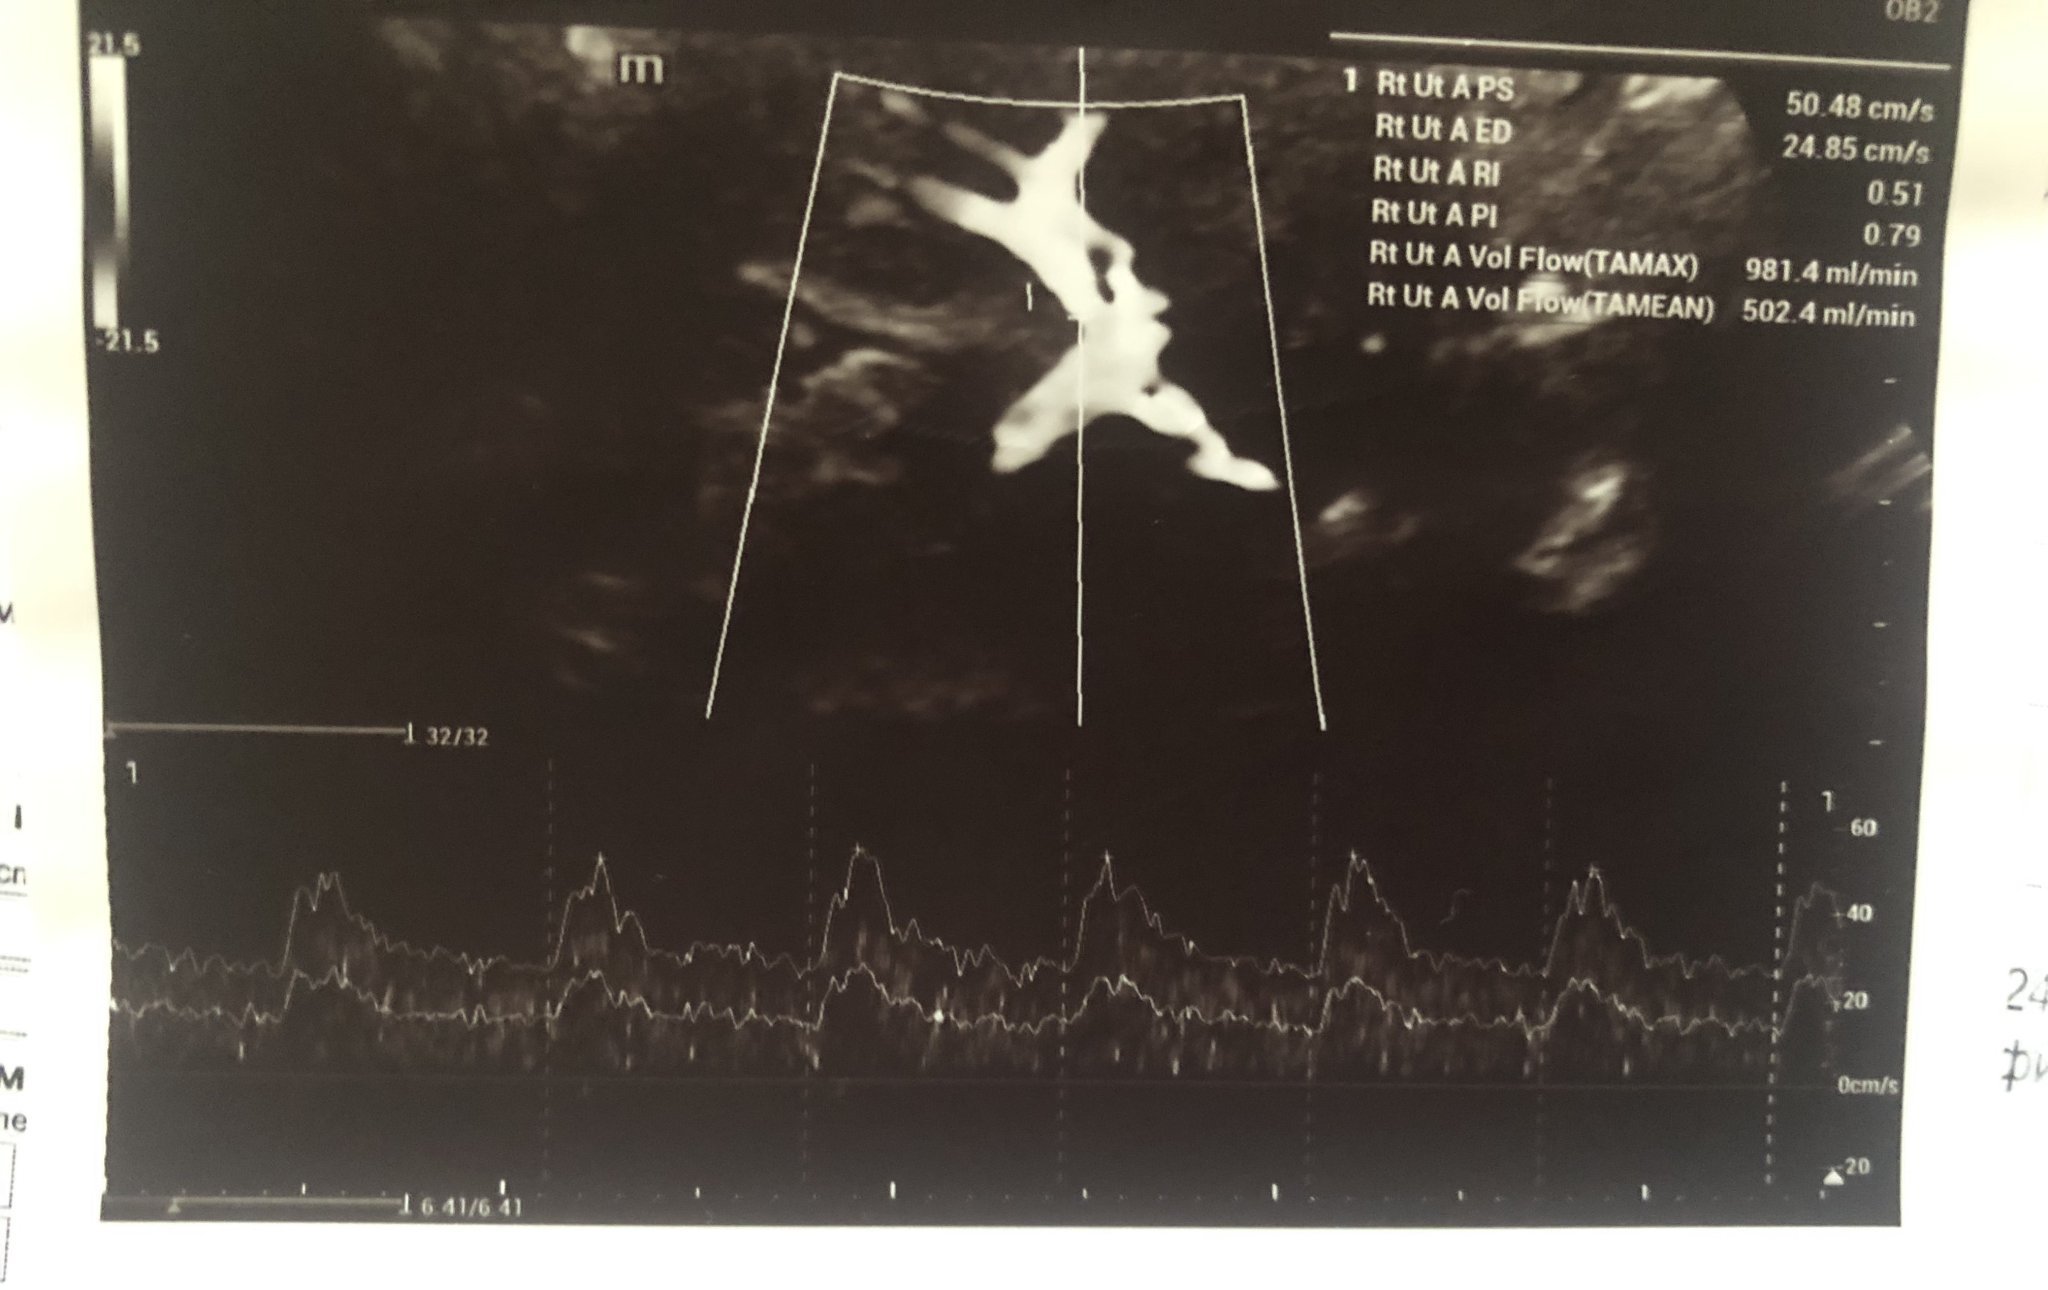

Ето така изглежда снимка от доплер на лява и дясна страна на маточна артерия, стойностите са описани отстрани като RI и PI. Освен това трябва да има и снимка от измерване на кръвотока към пъпната връв, който се означава на снимката (ако не се лъжа) като Umb A PI, съответно Umb A RI.

Мики, до колкото при мен проблемна е стойността на PI от 1,68. (В петък измерена в Токуда 1,59) мисля, че си супер.

Интересно, в моята ФМ пише само маточта артерия PI 1.38 еквивалент на 0.890MoM